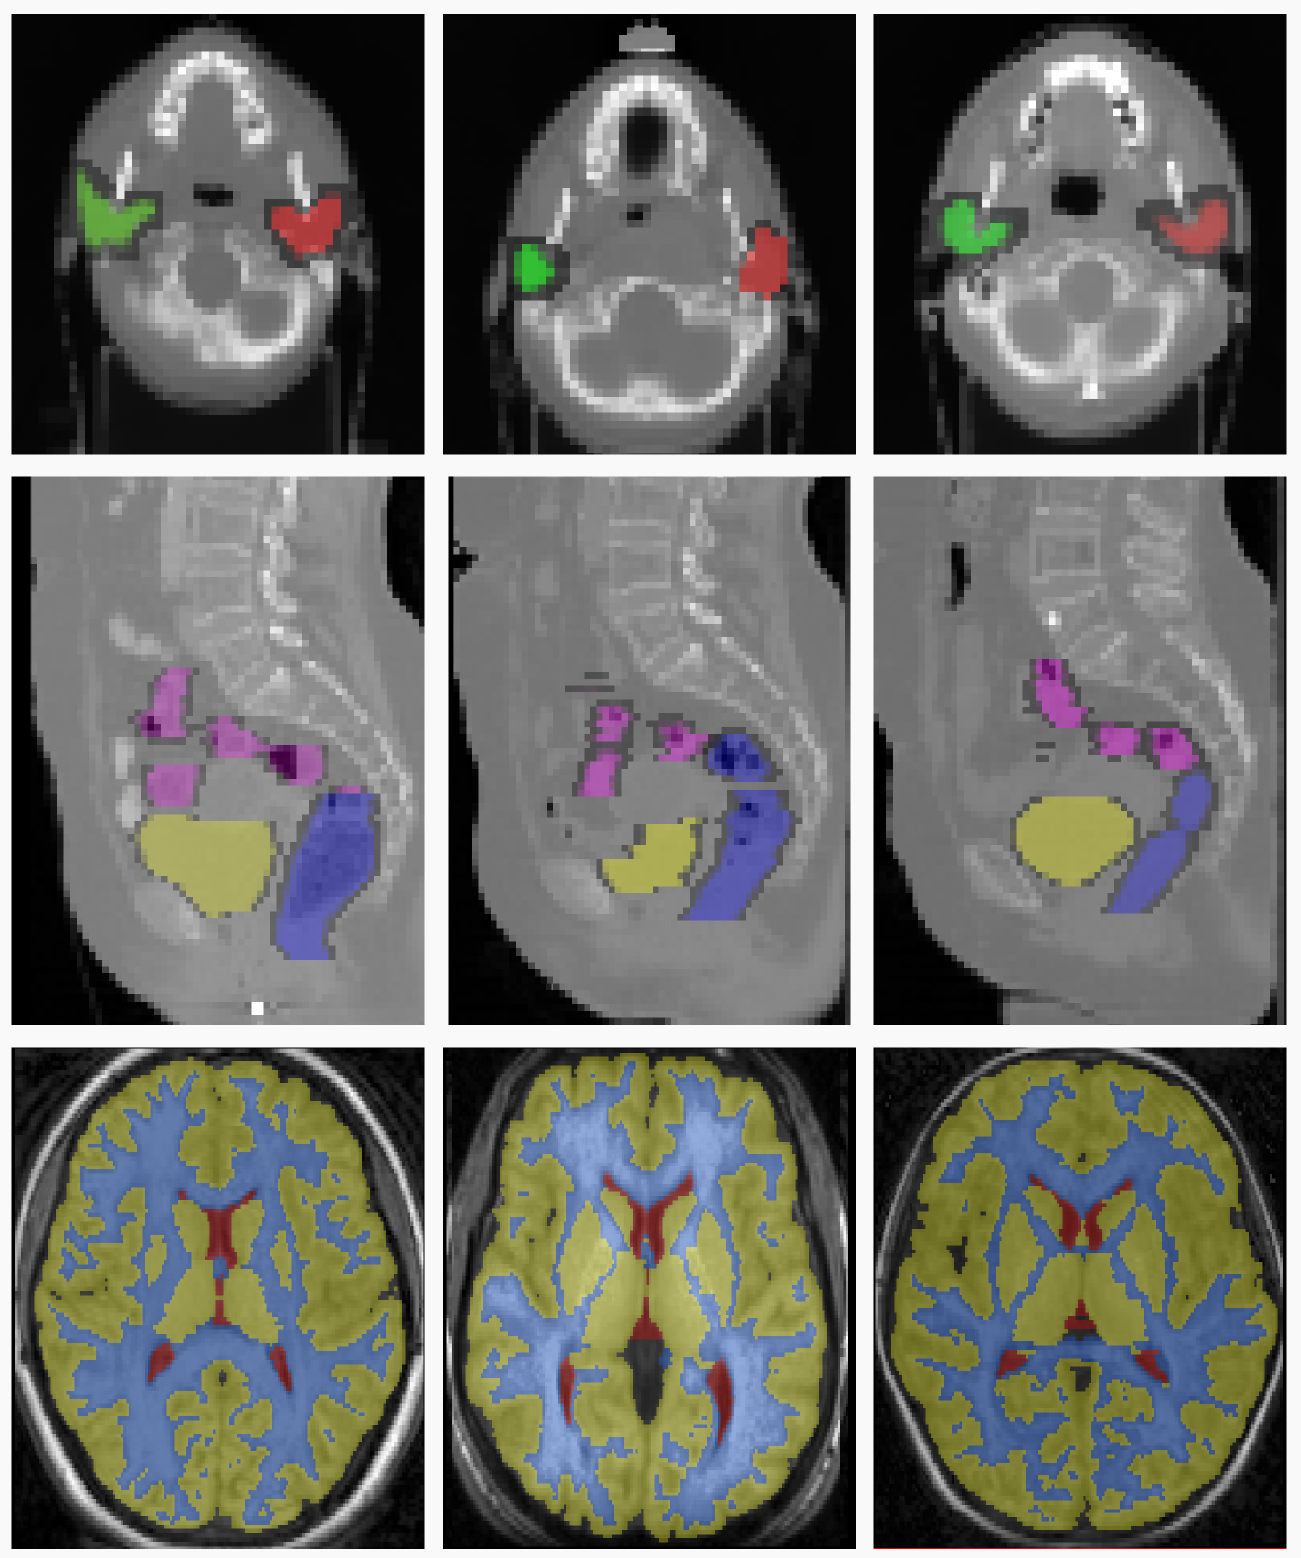

Refer to caption

Figure 2: Sample slices from three different volumes of the RT Parotids, RT Abdominal and IBSR datasets.The top row represents the sample slices from three different volumes of the RT Parotids dataset. The middle row represents the sample slices of the RT Abdominal dataset, and the last row represents the sample slices from the IBSR dataset.

RT Abdominal This dataset contains 555 CT volumes of abdomen for a particular patient captured with a time window of about 7 days during a radiotherapy treatment. Three organs have been manually segmented by the specialists: (1) sigmoid, (2) rectum, and (3) bladder. The dimensions of the volumes are 90×60×8090608090\times 60\times 80 voxels with a physical spacing of 3.673.673.67mm, 3.673.673.67mm, and 444mm, in x, y, and z axes, respectively (there are small variations depending on the volume). We generated a train dataset of 6 pairs and test dataset of 4 pairs. The results on the test dataset are shown in the Figure 5.b. IBSR We used images from the well known Internet Brain Segmentation Repository dataset, which consists of 181818 brain mri volumes, coming from different patients. Segmentations of three different brain structures are provided: white mater (WM), gray mater (GM), and cerebrospinal fluid (CSF). We used a downsampled version of the dataset to reduce the computation. The dimension of the volumes are 64×64×6464646464\times 64\times 64 voxels with a physical spacing of 3.753.753.75mm, 3.753.753.75mm, and 333mm in x, y, and z axes, respectively. To perform the experiments, we divided the 18 volumes in 2 folds of 9 volumes on each fold. This gave a total of 72 pairs per fold. We used an stochastic approach for the learning process, where we sample 10 different pairs from the training set, and we tested on the 72 pairs of the other fold. We run this experiment 3 times per fold, giving a total of 6 different experiments, with 72 testing samples and 10 training samples randomly chosen. Quantitative results on the test dataset are shown in Figure 5.c while qualitative results can be found in Figure 4.

Figure 2 shows the examples of the slices from the 3D3𝐷3D volumes corresponding to each dataset. In figures 3 and 4 we include some qualitative results on the three challenging datasets in order to highlight the effects of learning the weights of different metrics. In the first one (figure 3), we present the overlapping of the segmentation masks in different views for one registration case from RT Abdominal and RT Parotids datasets, using single and multi-metric approaches. The observed results are coherent with the numerical results reported in figures 5.a and b. We observe that multi-weight algorithm gives a better fit between the deformed and ground truth structures than the rest of the single similarity measures, which are over segmenting most of the structures showing a poorer registration performance. In the second graph (figure 4), we include results for the IBSR dataset. Extreme values (which mean high differences between the images) correspond to blue and red colors, while green indicates no difference in terms of intensity. Note how most of the big differences observed in the first column (before registration) are reduced by the multi-weight algorithm, while some of them (specially in the peripheral area of the head) remain when using single metrics.